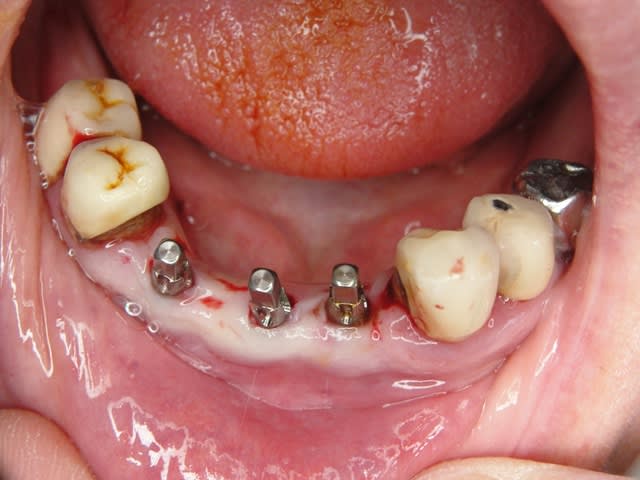

A défaut d'une chir en direct .. voilà une petite histoire en photos ou comment en 90 minutes passer d'un partiel résine à ...7 implants sur provisoires..stabilité primaire 60N grace à la technique MIMI ( oui.. post spécial ce Week end)..:)

Maintenant concernant la demande de scans : je poste ce cas, une patiente vient me voir avec son scan car elle a consulté d'autres "spécialistes" et on lui refuse la pose d'implant secteur 4 où alors avec greffe préalable..Ca se discute..pas de temps à perdre je sais faire autrement..

Avec la chir trans gingivale technique MIMI ( Oui..un post sur la technique bientôt ..) j'ai pu placer deux 3,5/8mm..aurai je eu le meme résultat avec un lambeau..j'en doute..Les couronnes sont en titane. Recul clinique 2 ans ras. Simple efficace rapide moins onéreux satisfaisant pour le praticien et la patiente..